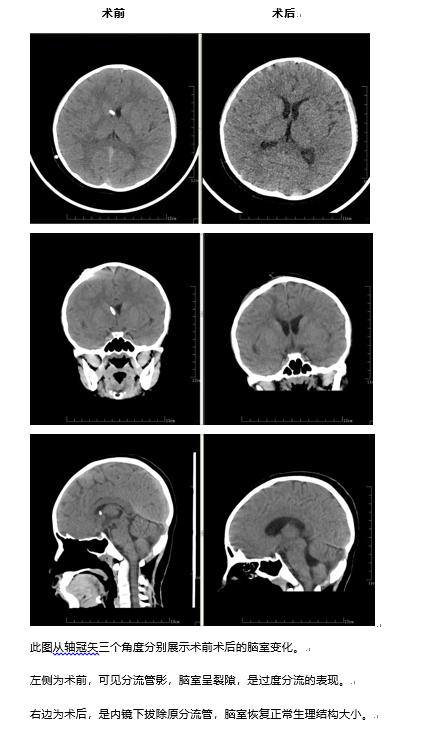

随后,肖庆团队为小宇在全麻下完成神经内镜检查术+神经内镜下第三脑室底造瘘术+脑室分流管去除术+脑室外引流术;术后6天,肖庆团队为小宇拔除脑室外引流,复查头颅CT脑室未见扩张,可以出院回家休养。